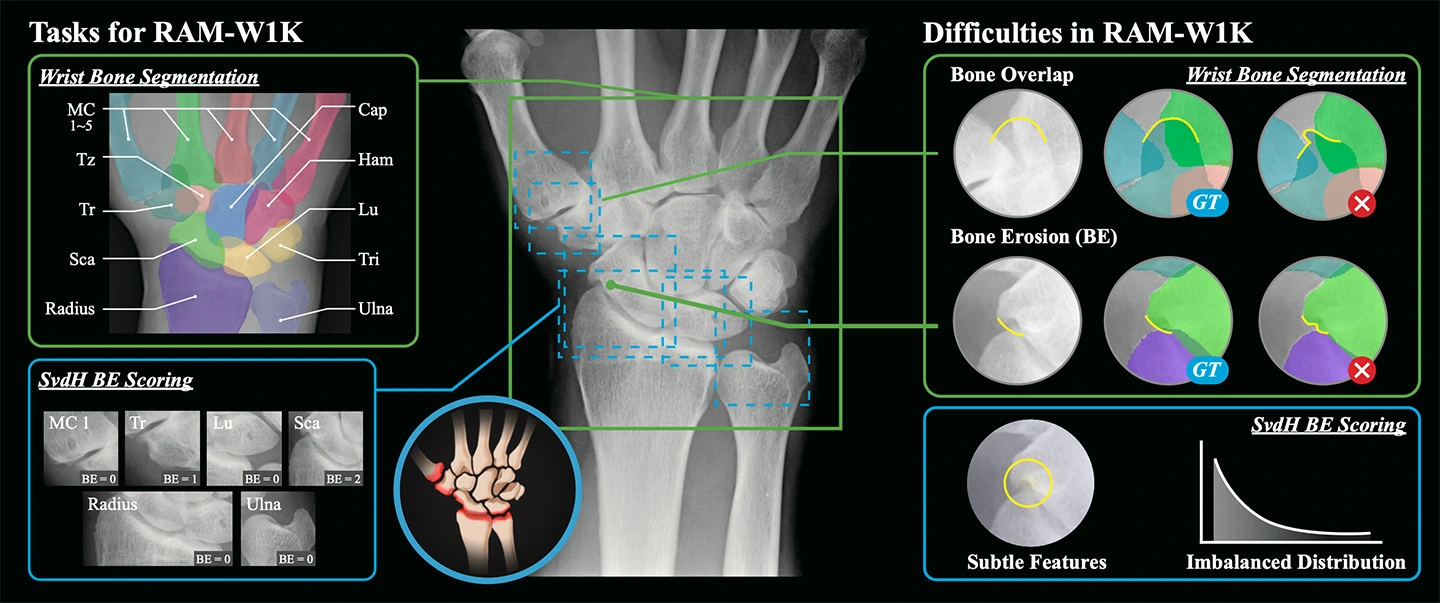

研究チームは手首X線画像に基づく初の公的マルチタスクデータセットRAM-W600を公開しました。対象は388名の患者のX線画像1,048枚で、618枚に骨インスタンスセグメンテーション注釈、800枚に標準的評価法である、Sharp/van der Heijde(SvdH)法による骨びらんスコアが付与されています。さらに、Unet、TransUNetなどの代表的な深層学習アーキテクチャや、SAMといった基盤モデルを用いた多様なAIベンチマーク実験が実施され、性能比較が行われました。

関節リウマチ(RA)は早期から手首関節を侵しやすい疾患であり、X線画像は広く用いられているものの、骨構造の複雑性や病的変形により、専門医による評価への依存度が高く、効率性に乏しいことがコンピューター支援診断(CAD)の発展を制限してきました。既存の公開データセットは、ピクセルレベルの分割アノテーションを欠くか、あるいは臨床的スコアが不足しており、RA特異的な研究ニーズを十分に満たしていませんでした。本研究では、RAに特化した世界初の手首関節X線画像多タスク大規模公開データセットRAM-W600を構築しました。本データセットは、手首関節骨のインスタンス分割及びSharp/van der Heijde(SvdH)骨侵食スコアという二つの主要タスクを網羅し、高品質なアノテーションとベンチマークを提供します。これにより、関節間隙狭小化の定量化や骨びらん検出といった多様な下流タスクを支援し、RA関連CAD研究のさらなる進展を後押しします。

本研究では、RAに特化した大規模公開データセット RAM-W600 を構築しました。本データセットは、4つの医療機関から収集した1,048枚の手首関節X線画像(388名の患者に由来)で構成され、そのうち618枚には骨単位のピクセルレベル分割アノテーションが、800枚には SvdH基準に準拠した骨侵食スコアが付与されています(図1)。研究チームはこれを基盤として多タスクベンチマーク実験を実施し、手首関節骨インスタンス分割及びBE分類に対する性能評価を行いました。評価には、Unet、Unet++、TransUNet、SwinUMambaなどの多様なディープラーニングアーキテクチャや、汎用モデル(SAM、MedSAM)を採用し、DSC、NSD、BACC、F1-scoreといった指標を用いて体系的に性能比較を行いました(図2)。

結果として、分割タスクでは教師ありモデルが総じて優れた性能を示し、特に SwinUMamba は DSC 97.75% という高い精度を達成しましたが、骨重なり部位や骨侵食領域では依然として顕著な精度不足が見られました。一方、汎用モデルのSAMは明らかに劣る結果となりました。BE分類タスクでは、モデル全体の性能は限定的であり、最高でも平衡精度は約52.6%にとどまり、F1-scoreも低値で、クラス不均衡に起因する感度不足が課題として確認されました。総じて、RAM-W600はRA手首関節画像に対する高品質な分割・スコアリング資源を提供するとともに、既存手法が複雑な臨床病変に直面した際の限界を浮き彫りにし、今後より堅牢なCAD技術の開発に向けた基盤を提示しています(図3)。

図3. 公開されたマルチタスクデータセットとAIベンチマーク。